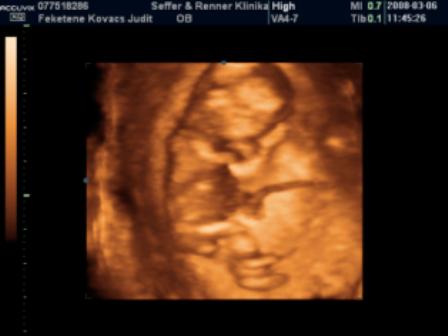

Mi holnap este megyünk.Ilyenkor még végigjárjuk a nagyszülőket + egy kis vásárolgatás, este 9-től hamarabb nem hiszem, hogy hazaérünk, de jövök majd a beszámolóval és a fotóval.